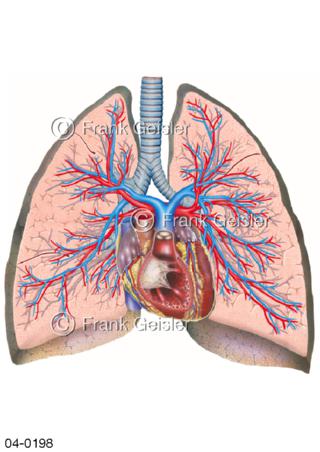

Bildergalerie Topografie Organe

Bilder zur topografischen Anatomie, die Lage der Organe und die Strukturen nach ihren räumlichen Lagebeziehungen zueinander, Übersicht der inneren Organe im Kopf und im Rumpf, Topografie der Organe im Brustraum (Thorax) und im Bauchraum (Abdomen)